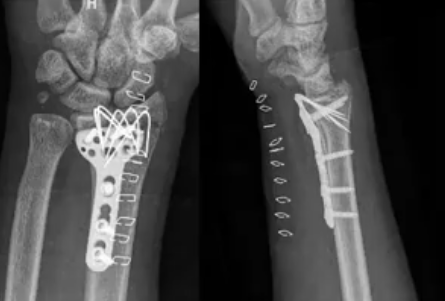

5. The Fracture Every Ortho Should Know – Distal Radius Volar Rim By Dr. Shailesh Pai

This fracture involves a tiny anatomical area yet creates a massive biomechanical challenge.

In this lecture, understand:

• Why volar rim fractures are so critical

• Stability principles

• Key management strategies

• Common errors and how to avoid them

Short, crisp, high-yield.